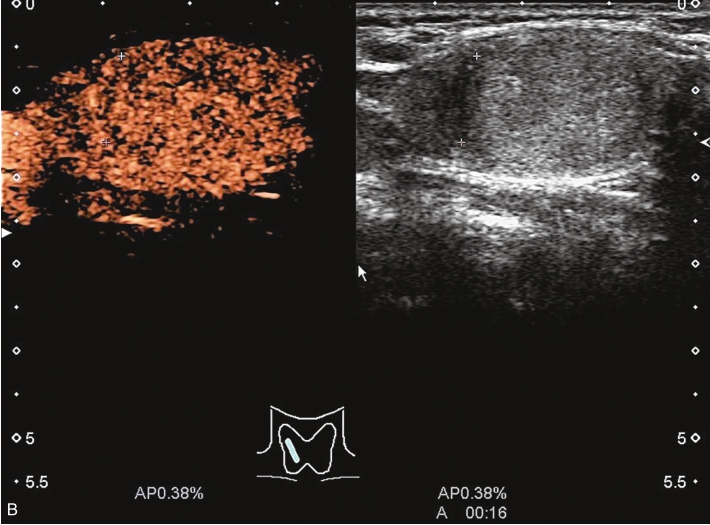

患者71岁女性,因“发现甲状腺包块1.5年,颈部疼痛5个月”入院。5个月前间断出现吞咽后梗阻,颈部疼痛。

图像描述:右叶中下部见一等回声结节,边界清,形态规则,周边见低回声晕,内回声欠均;结节内见较丰富点条状血流信号,周边见环状血流信号,见图1-3-24。

图像描述:甲状腺右叶中下部结节早于周围腺体组织增强,达峰后呈不均匀高增强,周边见高增强环,消退与周围腺体组织同步,仍呈稍高增强,见图1-3-25。

甲状腺嗜酸细胞腺瘤超声造影与其他腺瘤表现基本一致,呈膨胀性生长,包膜完整。因供应其生长的动静脉被增大的瘤体挤压至周边形成丰富的包绕血管,并向内部逐级发出分支。因此超声造影常从周边开始向内部不均匀增强,可见周边环状增强,内部轻度增强或等增强,强度小于周边,达峰时结节整体呈高增强,而廓清时结节通常晚于相邻甲状腺实质呈缓慢消退。

图1-3-24 甲状腺嗜酸性细胞腺瘤常规超声声像图

A.甲状腺右叶等回声结节纵切面灰阶超声图像;B.甲状腺右叶等回声结节CDFI图像

图1-3-25 甲状腺嗜酸性细胞腺瘤超声造影图

A.甲状腺结节造影后12s图像;B.甲状腺结节造影后16s图像;C.甲状腺结节造影后30s图像